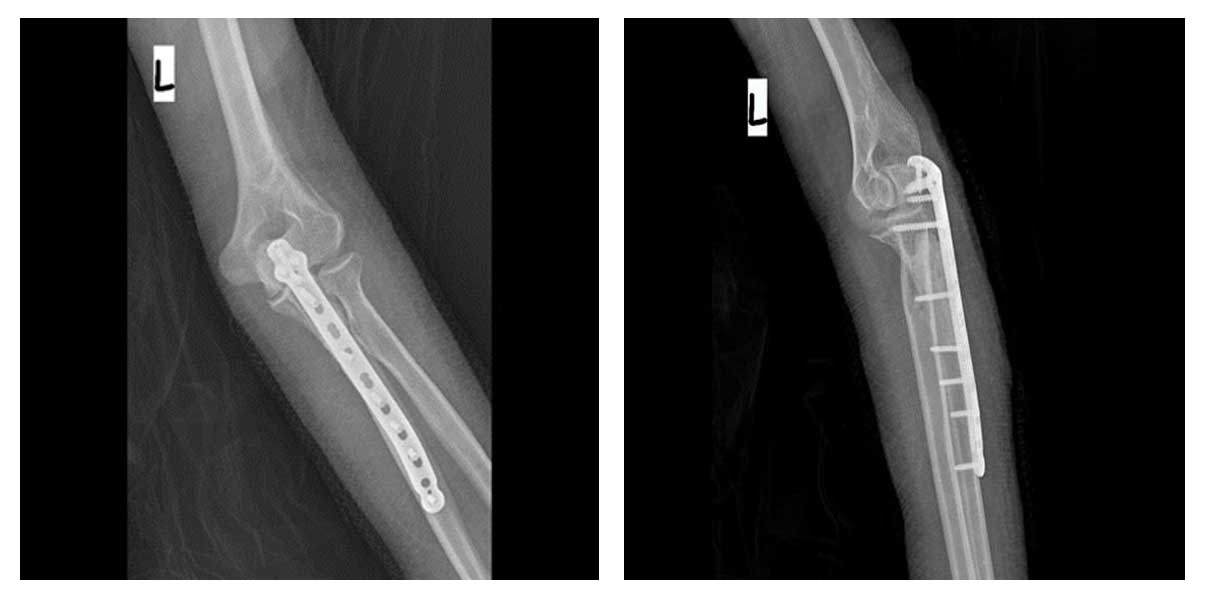

Kemikteki tümörlü doku temizlendikten sonra oluşan boşluk kemik çimentosu (PMMA) ile dolduruldu ve bölge anatomik titanyum plak ile stabilize edilerek kırık riski ortadan kaldırıldı.

Ameliyat Esnası: Tümörün çıkarılması, titanyum plak ile fiksasyon ve oluşan boşluğun kemik çimentosu ile güçlendirilmesi görülmekte.

Ameliyat Sonrası: Röntgende kemikteki tümörün temizlenmesi sonrası oluşan boşluğun kemik çimentosu ile doldurulması ve anatomik titanyum plak ile güçlendirilmesi görülmekte.